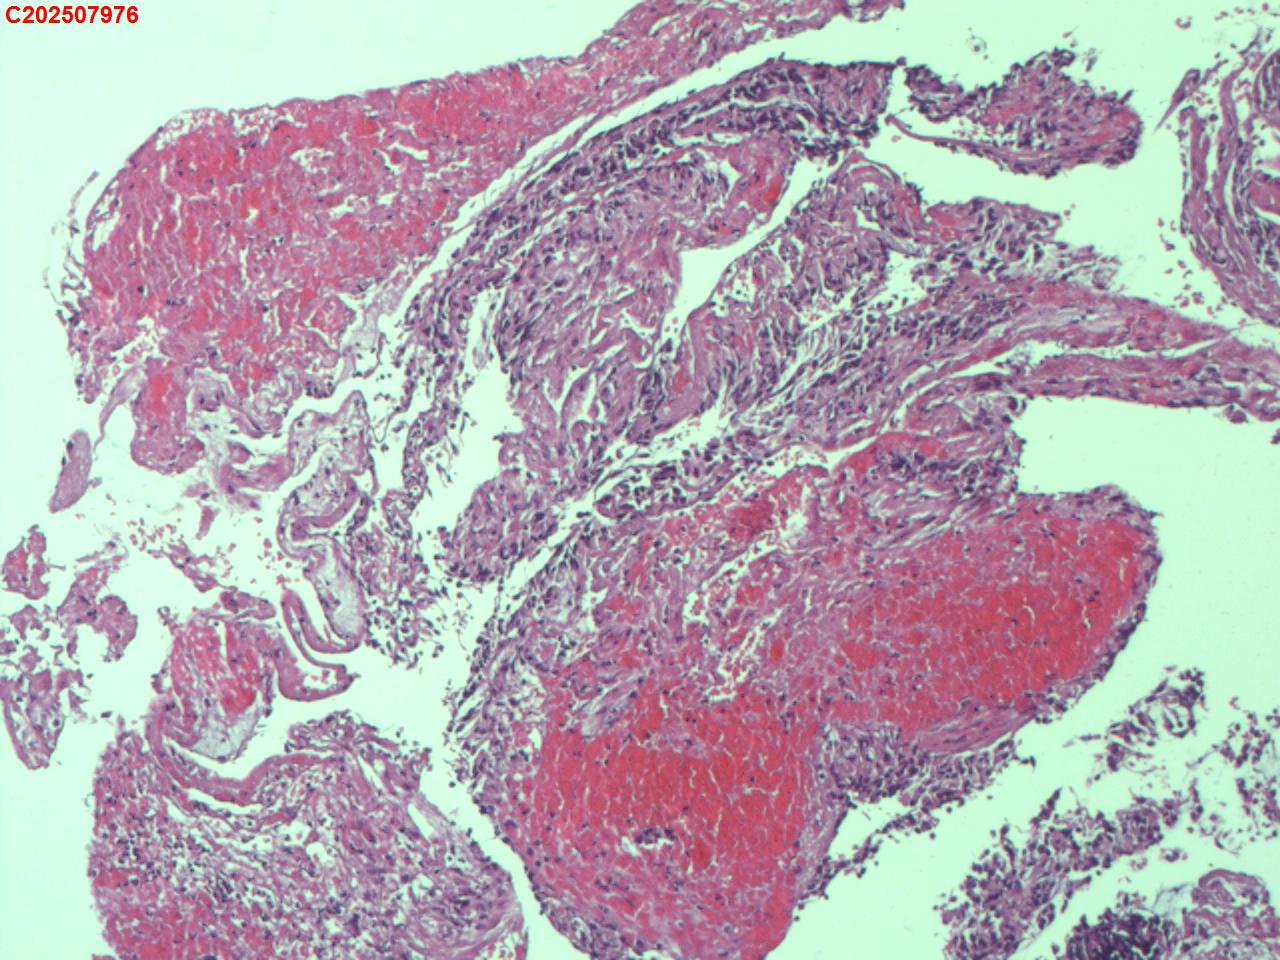

右肺上叶开口处 气管镜咬检

右肺上叶开口上缘处可见肉芽增生,予咬检。

图4

感觉:炎性纤维组织增生